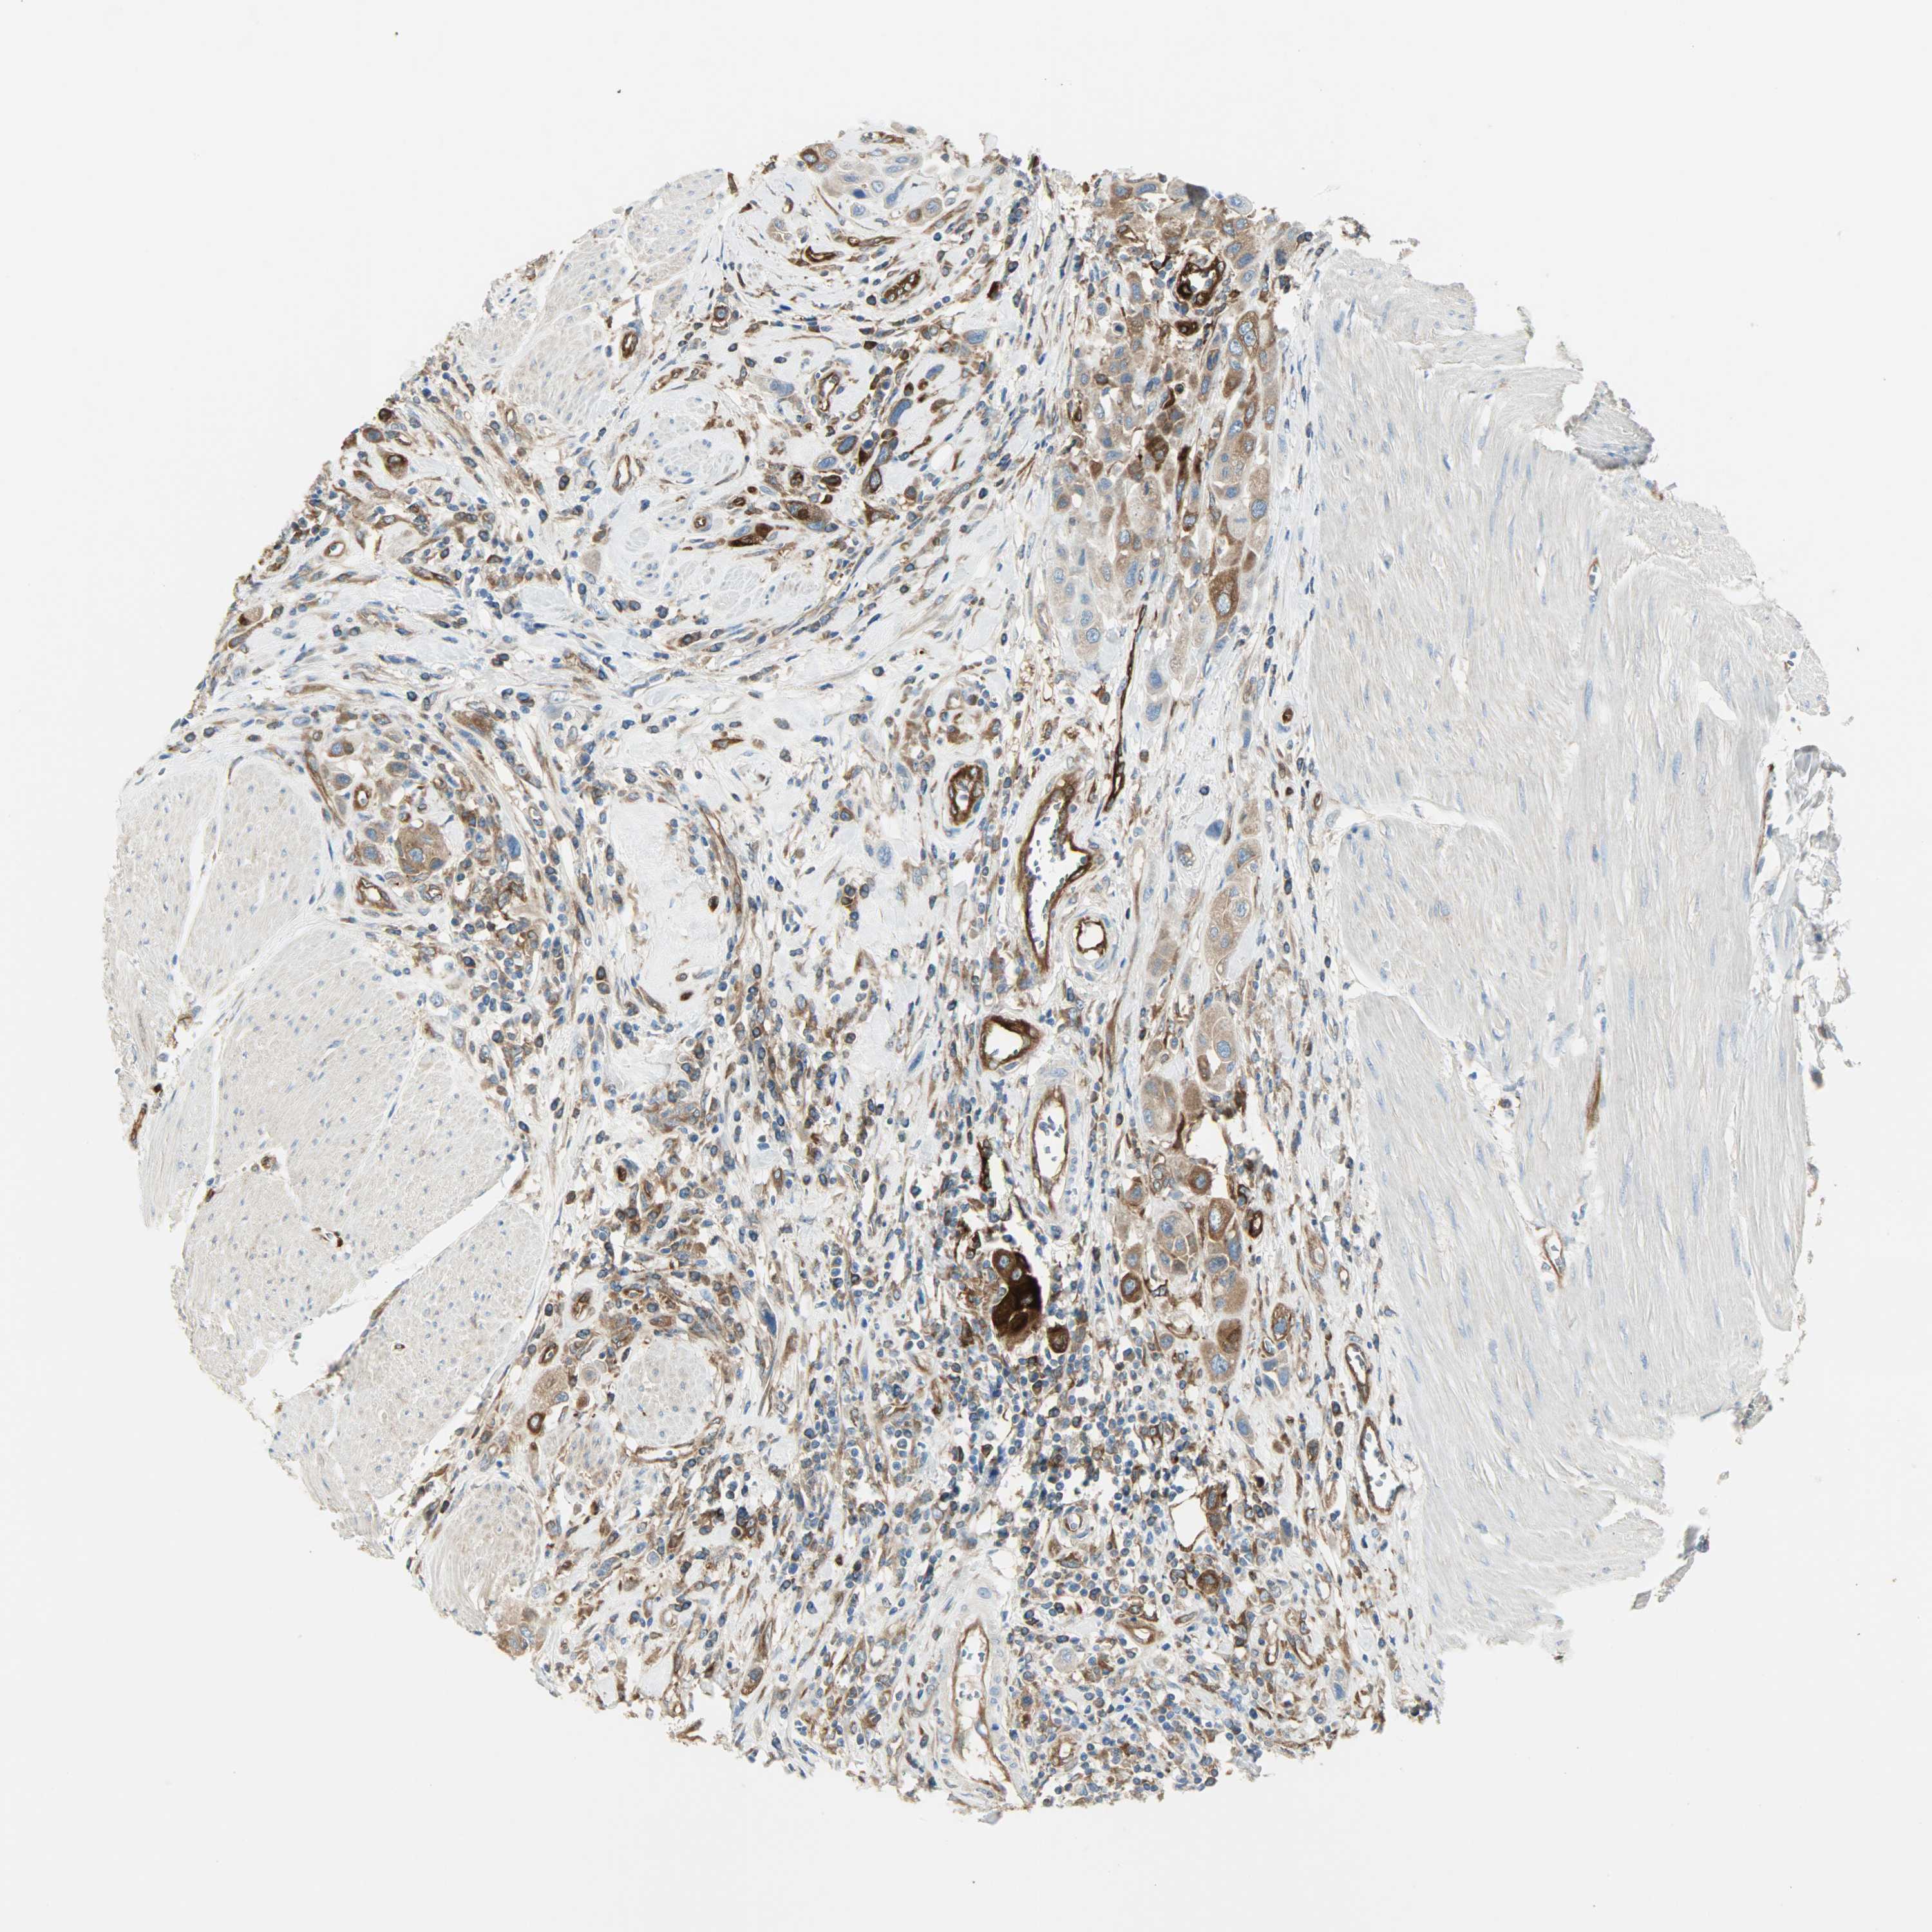

UROTHELIAL CANCER - Protein expressioni

A mouse-over function shows sample information and annotation data. Click on an image to view it in a full screen mode. Samples can be filtered based on level of antibody staining by selecting one or several of the following categories: high, medium, low and not detected. The assay and annotation is described here.

Note that samples used for immunohistochemistry by the Human Protein Atlas do not correspond to samples in the TCGA dataset.

Antibody stainingi

Antibody staining in the annotated cell types in the current human tissue is reported as not detected, low, medium, or high, based on conventional immunohistochemistry profiling in selected tissues. This score is based on the combination of the staining intensity and fraction of stained cells.

Each image is clickable and will lead to virtual microscopy that enables deeper exploration of all samples and also displays staining intensity scores, fraction scores and subcellular localization as well as patient and tissue information for each sample.

Antibody HPA005573

Staining

High

Medium

Low

Not detected

Intensity

Strong

Moderate

Weak

Negative

Quantity

>75%

75%-25%

<25%

None

Location

Nuclear

Cytoplasmic/membranous

Cytoplasmic/membranous,nuclear

Urothelial carcinoma, High grade

Urothelial carcinoma, Low grade